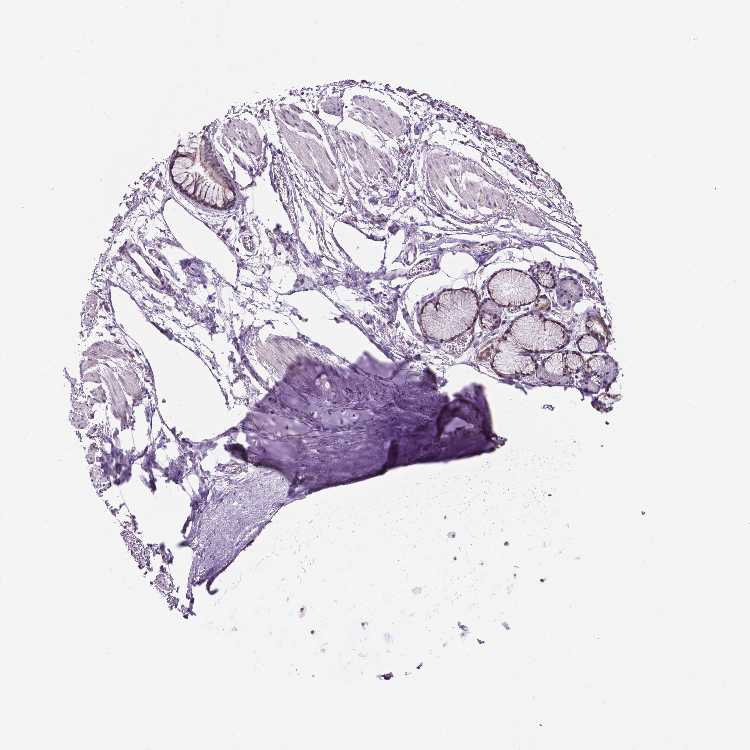

SOFT TISSUE 1 - Antibody stainingi

Antibody staining in the annotated cell types in the current human tissue is reported as not detected, low, medium, or high, based on conventional immunohistochemistry profiling in selected tissues. This score is based on the combination of the staining intensity and fraction of stained cells.

Each image is clickable and will lead to virtual microscopy that enables deeper exploration of all samples and also displays staining intensity scores, fraction scores and subcellular localization as well as patient and tissue information for each sample.

Antibody HPA067203Antibody CAB025507Antibody CAB073546

Chondrocytes Not detectedMedium-

Fibroblasts Not detectedMediumMedium

Peripheral nerve -Medium-